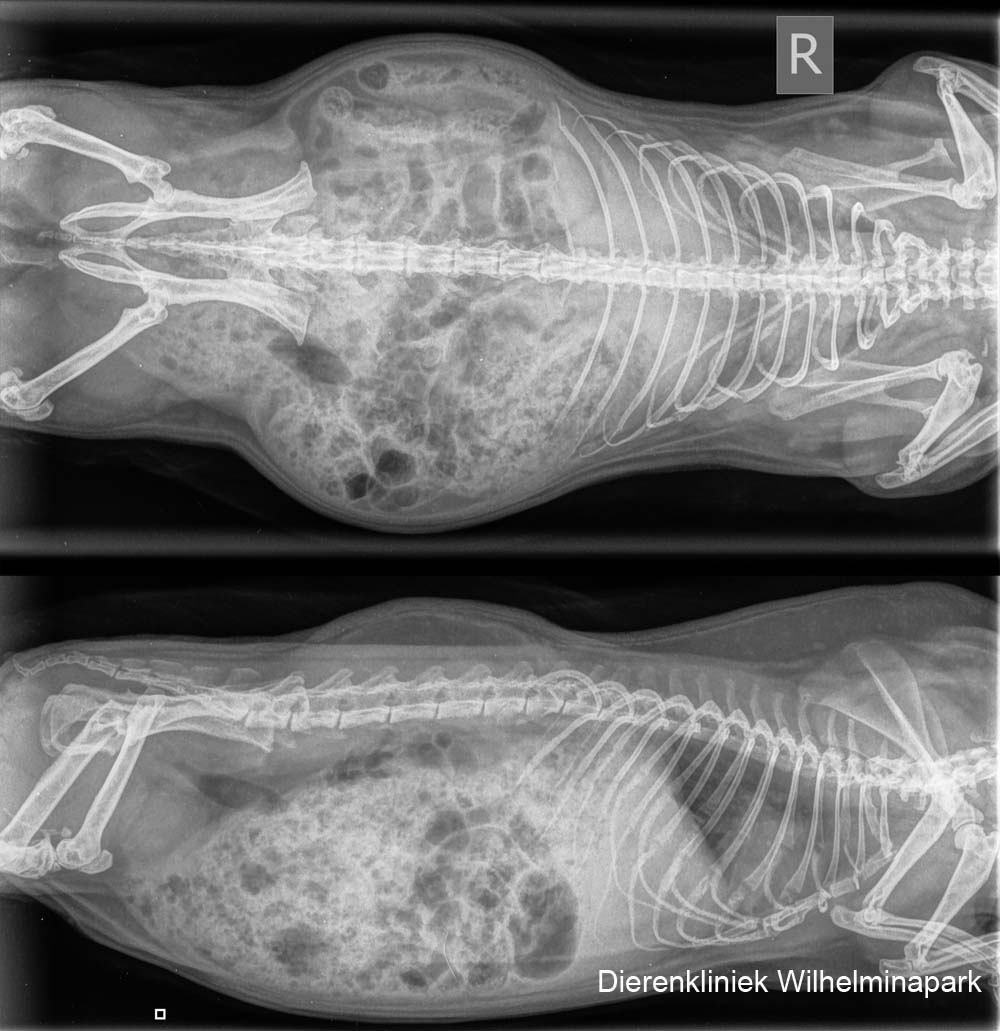

Tweety had al drie soorten antibioticum gekregen, maar deze sloegen onvoldoende aan.

Bij cavia Tweetie is er er op de röntgenfoto's een aanwijzing van een hartprobleem te zien.

We hebben de röntgenfoto's laten beoordelen: er is een verdenking van een pericard overvuulling. Het hart is vergroot op de röntgenfoto, het advies is om een echo te maken. Met een echografisch onderzoek is een pericardovervulling goed te zien. Er zit dan vocht tussen het hart en het hartzakje.

We hebben röntgenfoto's gemaakt van de buikholte en de borstholte.

We hebben röntgenfoto's laten beoordelen. Er komt een verdenking van tumoruitzaaiingen uit de beoordeling naar voren. June werd minder benauwd en heeft nog een jaar geleefd, ze kreeg een pijnstiller en ontstekingsremmend middel.